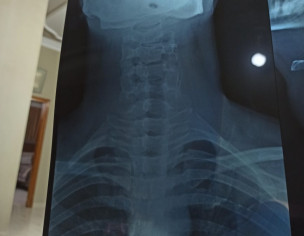

I have been stiff neck problems for quite sometime now where I wake up with a stiff neck which leads to headaches. I work in IT and have a desk job 9 hours a day. I have recently had my neck X-ray done on the advice of my doctor. I seek help as I will not be able to visit my doctor due to work. Doc works in the weekdays and so do I. I need someone qualified to take a look at my x-ray and tell me if there is anything wrong. I would be grateful. Bless you!

Attach Photo here: